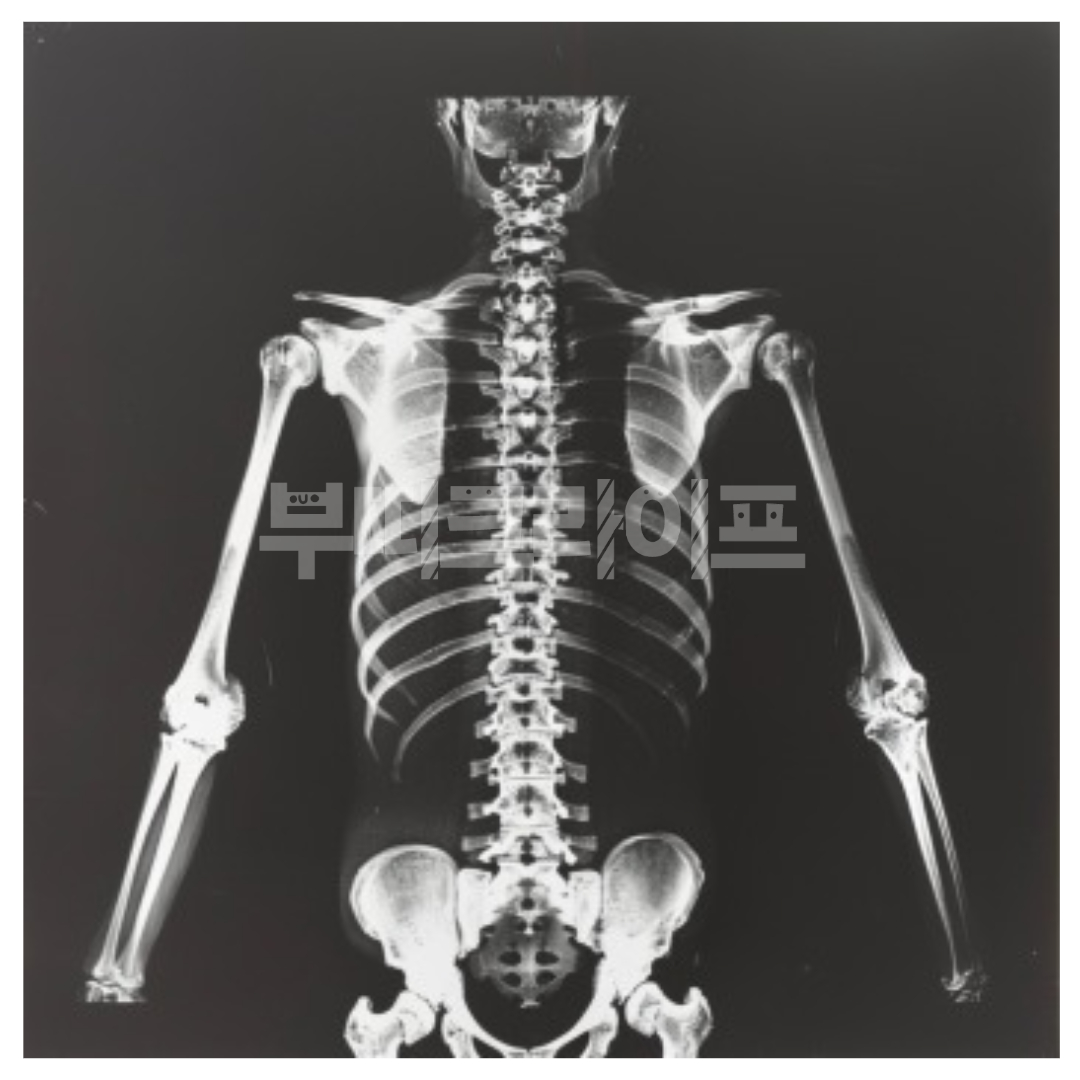

어깨는 우리의 팔과 상체를 연결하는 중요한 관절로, 무리한 동작이나 잘못된 자세로 쉽게 부담을 받을 수 있는 부위입니다. 그런데 어깨 통증의 원인은 단순히 피로 때문만은 아닐 수 있어요. 사실, 이 불쾌한 통증에는 수많은 원인이 숨겨져 있습니다. 오늘은 어깨 통증의 다양한 원인 15가지를 이야기해 보려고 합니다.

어깨 통증은 단순히 지나가는 통증일 수도 있지만, 때로는 몸이 보내는 중요한 신호일 수 있습니다. 오늘 살펴본 15가지 원인들처럼 어깨 통증은 다양한 요인으로 인해 발생할 수 있고, 각각의 원인에 따라 대처법도 달라집니다.